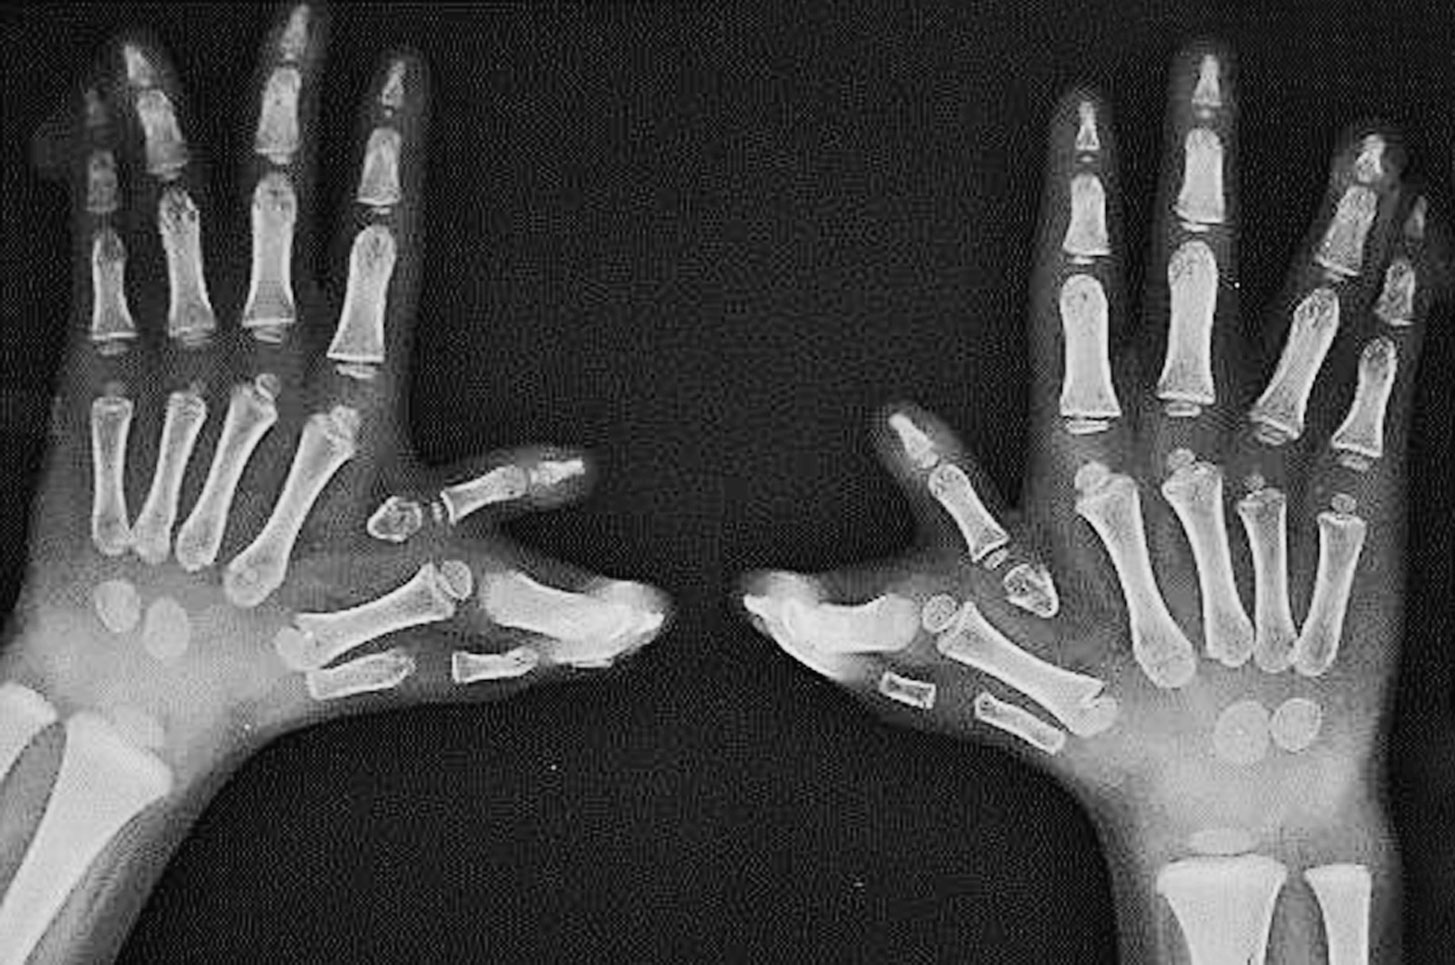

图2-5-2 中央型及尺侧多指并存病例2

A.复杂性多并指畸形,有家族遗传史;B.X 线片显示双侧小指多指,中指多指畸形,骨关节结构严重发育紊乱